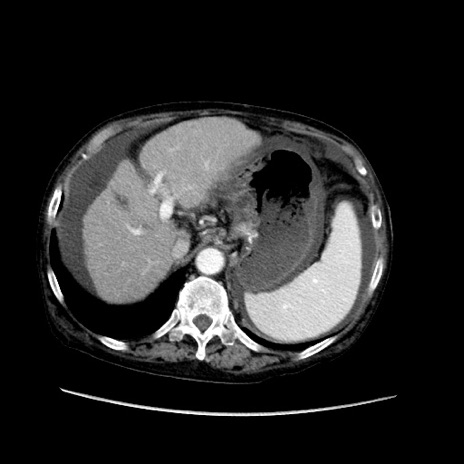

症例31(横断像)

【症例】80歳代 女性

【主訴】腹部膨満感

【現病歴】他院にて肝硬変にてフォロー中。1週間前から便秘、腹部膨満感、臍部腫瘤あり受診となる。

【既往歴】肝硬変

【身体所見】腹部膨隆あり、皮膚変化なし、疼痛なし。

【データ】WBC 4600、CRP 0.25